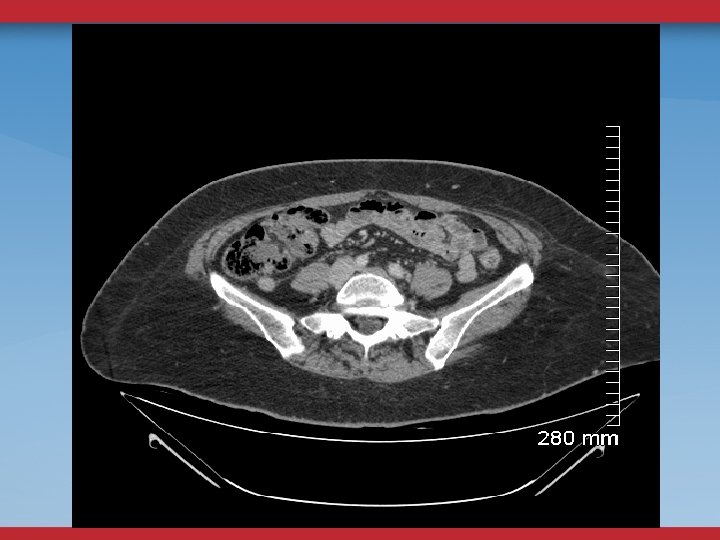

CT/MR VENOGRAMS - HELP WITH ANATOMIC DETAIL - DO NOT EVALUATE FLOW - DEPENDENT UPON FACILITY AND RADIOLOGIST INTEREST - CT— TIMING OF CONTRAST INJECTION/FLOW ISSUES

DEFINITIVE DIAGNOSTIC/THERAPEUTIC PROCEDURES VENOGRAMS UG sheath placement Femoral, Pop, PTV Flow, Collaterals

VENOGRAMS FEMORAL INFLOW FILLING DEFECTS WILL MISS SOME STENOSES, WEBS

INTRAVASCULAR ULTRASOUND THE ANATOMIC GOLD STANDARD USUALLY BILATERAL IFV/IVC CHOOSE DIAMETER/LENGTH OF BALLOON/STENT POST-STENTING ASSESSMENT